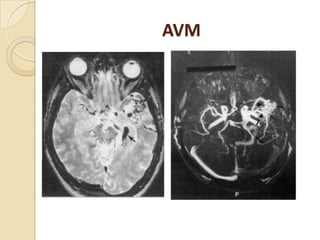

A-V Malformations

 Secondary role to digital subtraction

angiography.

 The typical AVM appears on spin-echo MRI as a

cluster of focal round lesions or serpentine areas

of signal void

 3D CE MRA is superior to 3D TOF MRA and

equivalent to subtraction angiography in 70-

90%of cases in depicting AVM components.

AVM